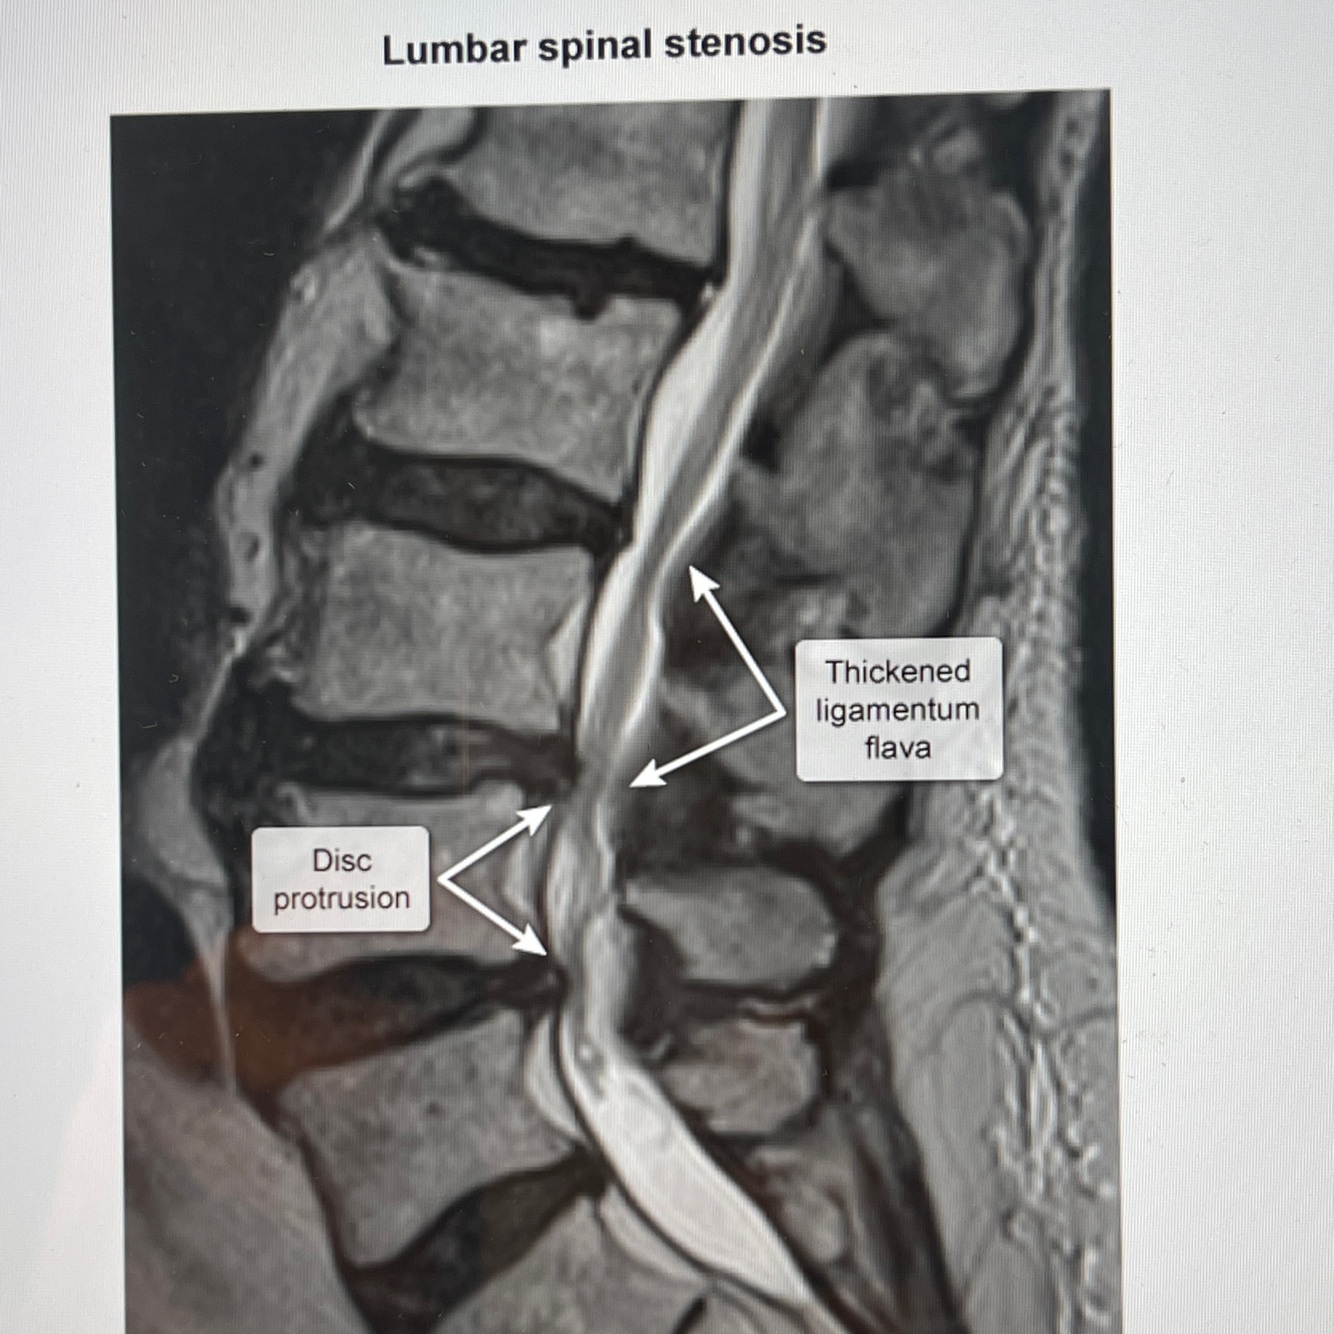

How well did you know this?